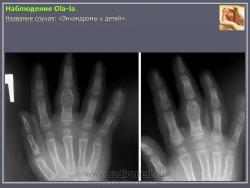

Энхондрома (син.: хондрома, центральная хондрома) — доброкачественная хрящевая опухоль, расположенная в костномозговом канале (интрамедуллярно). Встречается в 10 % случаев от общего числа доброкачественных опухолей костей. Считается, что она возникает из эктопически расположенных островков хряща, отщепившегося от пластинки роста на ранних этапах онтогенеза. В ряде случаев опухоль остается бессимптомной и обнаруживается случайно при рентгенологическом исследовании. В других случаях возникают боль и припухлость. Обычно болезненными становятся все энхондромы фаланг. Наиболее частая локализация: фаланги, главным образом, пальцев кистей, проксимальный конец плечевой кости, проксимальный или дистальный концы бедренной кости. При рентгенологическом исследовании в энхондроме определяются просветления с участками минерализации. Тень кости становится более широкой, кортикальный слой сохраняет целостность, но истончается. В редких случаях энхондрома имеет вид эксцентрически растущего экзофитного новообразования. Макроскопически опухоль представляет собой голубовато-белую полупрозрачную хрящевую ткань, в которую вкраплены желтоватые участки обызвествления. Опухоль состоит из отдельных хрящевых узелков, диаметр которых варьирует в пределах 1 см.

Энхондроматоз (син, болезнь Оллье) — редкая врожденная патология, не передающаяся по наследству, при которой у больных имеется множество доброкачественных хрящевых опухолей, главным образом на конечностях. Пораженная конечность укорачивается и деформируется. После завершения полового созревания заболевание не прогрессирует. Возможна малигнизация, которая отмечается в возрастном промежутке 13—69 лет. Локализация: энхондромы обнаруживаются в метафизах, диафизах, эпифизарных пластинках и суставных хрящах. Это интракортикальные и/или периостальные поражения в виде отдельных опухолей, не сливающихся друг с другом. Им присущ основной признак энхондроматоза — богатство клетками (гипериеллюлярность), причем встречается много двуядерных хондроцитов. И гиперцеллюлярность, и цитологическая атипия при энхондроматозе выражены значительнее, чем при солитарной энхондроме.